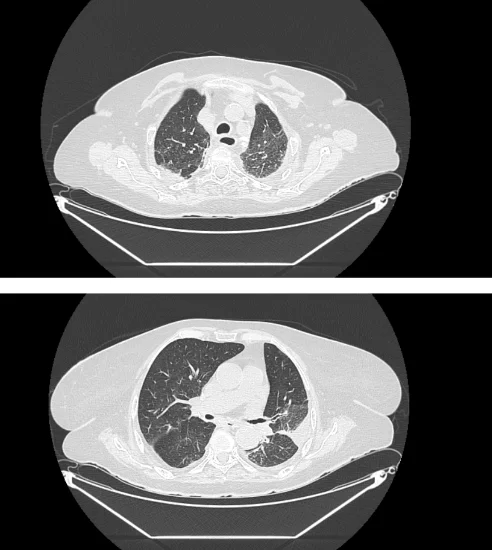

___В декабре 2024 года в пульмонологическое отделение по линии скорой медицинской помощи доставлена пациентка Б., 87 лет, с жалобами на боли в грудной клетке при дыхании, общую слабость. Заболевшей себя считает 6 дней назад, когда впервые появились боли в груди. По этому поводу принимала нестероидные противовоспалительные препараты. Обращает на себя внимание, что 4 дня назад выписана из другого стационара, где проходила лечение по поводу внебольничной двусторонней пневмонии. Госпитализирована в отделение пульмонологии с диагнозом «пневмония». На фоне стартовой терапии пациентка прошла с отрицательной динамикой. Основная причина ухудшения – пароксизм фибрилляции предсердий с развитием церебральной и сердечно-сосудистой недостаточности. В этой связи переведена в отделение анестезиологии и реанимации, где потребовалось протезирование дыхательной функции на фоне нестабильной гемодинамики. Путем объемного экстренного дообследования исключена тромбоэмболия легочной артерии. Больная погружена в медикаментозный сон, переведена на ИВЛ. Обследована, пароксизм фибрилляции купирован. Однако к этому моменту правое легкое было поражено на 100%, а в левом имелись выраженные очаги повреждения.

___Вместе с тем, постепенно состояние пациентки удалось относительно стабилизировать. В течение 2х недель параметры вентиляции несколько смягчились. Однако степень повреждения была такова, что полный отказ от ИВЛ был по-прежнему невозможен.

___Предпринято 5 попыток реабилитационных мероприятий в условиях отделения анестезиологии и реанимации. Последняя попытка дала необходимый эффект – пациентка все увереннее и увереннее дышала самостоятельно. Сначала самостоятельно подключенная к аппарату ИВЛ. Затем с помощью высокопоточной вентиляции. Затем на кислородной маске. Полностью отключиться от ИВЛ удалось только на 45 сутки. Все эти 45 дней специалисты поддерживали пациентку в борьбе с легочным повреждением, ежедневно проводя часы за попытками общей активизации. Наконец, состояние больной позволило получать лечение в условиях отделения пульмонологии. Пневмония разрешилась.